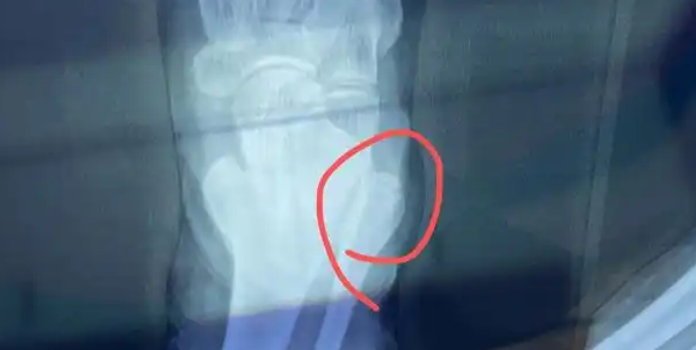

骨裂根据骨折位置的不同,分为纵行骨折、横行骨折、斜行骨折和螺旋骨折等。轻微骨裂通常指的是非移位性骨折或者是完全性、不影响四肢功能的骨折。这种骨裂一般不需要手术治疗,可以选择保守治疗方法。